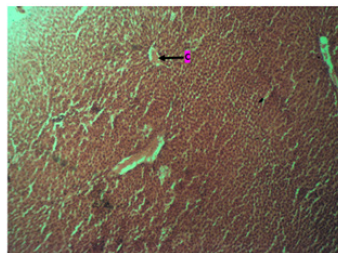

The histological result of the study in control animals, shows a portal triad (P) and central vein (C) with many surrounding hepatocytes with sinusoids. And the tissue appears normal as seen in (Plate 1).

Plate 1: Photomicrograph of the liver in the control group showing a portal triad (P) and central vein (C). There are many surrounding hepatocytes with sinusoids. Tissue appears normal. H & E. X200.

The liver's typical cellular and tissue architecture was demonstrated by the study's findings. The liver is made up of parenchymal cells, the portal triad (P), the central vein (C), and numerous other non-parenchymal cell types, all of which are important. In addition to being the target of autoimmune liver disorders, biliary epithelial cells also play a crucial role in the coordination of many immune cells involved in both innate and acquired immunity (Plate 1). Our current study's outcome is consistent with the conclusions of [9].

The study's histology findings for the control animals display a central vein (C) and portal triad (P) with many hepatocytes with sinusoids surrounding them. As can be seen in (Plate 1), the tissue looks normal. However, in the low dose group, the central vein (C) was visible, along with many surrounding hepatocytes with sinusoids, and the parenchyma displayed pseudorosettes tissue, as can be seen in (Plate 2) above. These results are consistent with research by Olagunju, et al. (2020) [18], which found that giving plantain weed extract reduced several markers of inflammation brought on by liver injury. On the other hand, the results of administering a high dose of aqueous extract from Musa Paradiasica reveal a central vein (C) surrounded by many hepatocytes with sinusoids. Additionally, as Plate 3 illustrates, the tissue looks normal. This finding is consistent with Redoy, et al.'s [18] research from 2021, which found that plantain weed extract significantly reduced inflammation and liver enzymes to prevent liver damage.